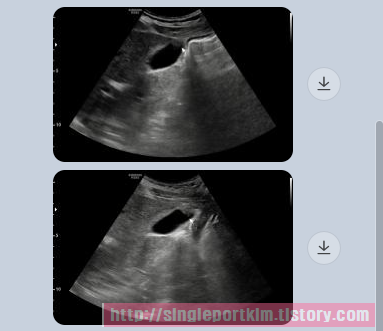

최근 동네 내과에서 복부초음파 검진시 담낭선근종증 의증인데 크기가 큰편이라며

큰 병원에 방문해 보라는데 사진상 절제가 필요한지 판단이 가능하실까요?

안녕하세요 김정윤 원장입니다. 담낭 선근종증은 담낭벽에서 자라는 혹입니다.

선근종이 자랄수록 담낭벽이 두꺼워지져 담낭 수축 능력이 줄어 들게 됩니다.

담낭 기능이 저하되면 담낭은 소화와 관련되기에 소화 능력 저하 그리고

담낭 수축력 저하에 의한 담낭내 담즙 정체에 의한 담석이 생길 경우 해당

담낭은 더이상 사용이 어렵다고 판단되어 수술적 절제를 하게 됩니다.